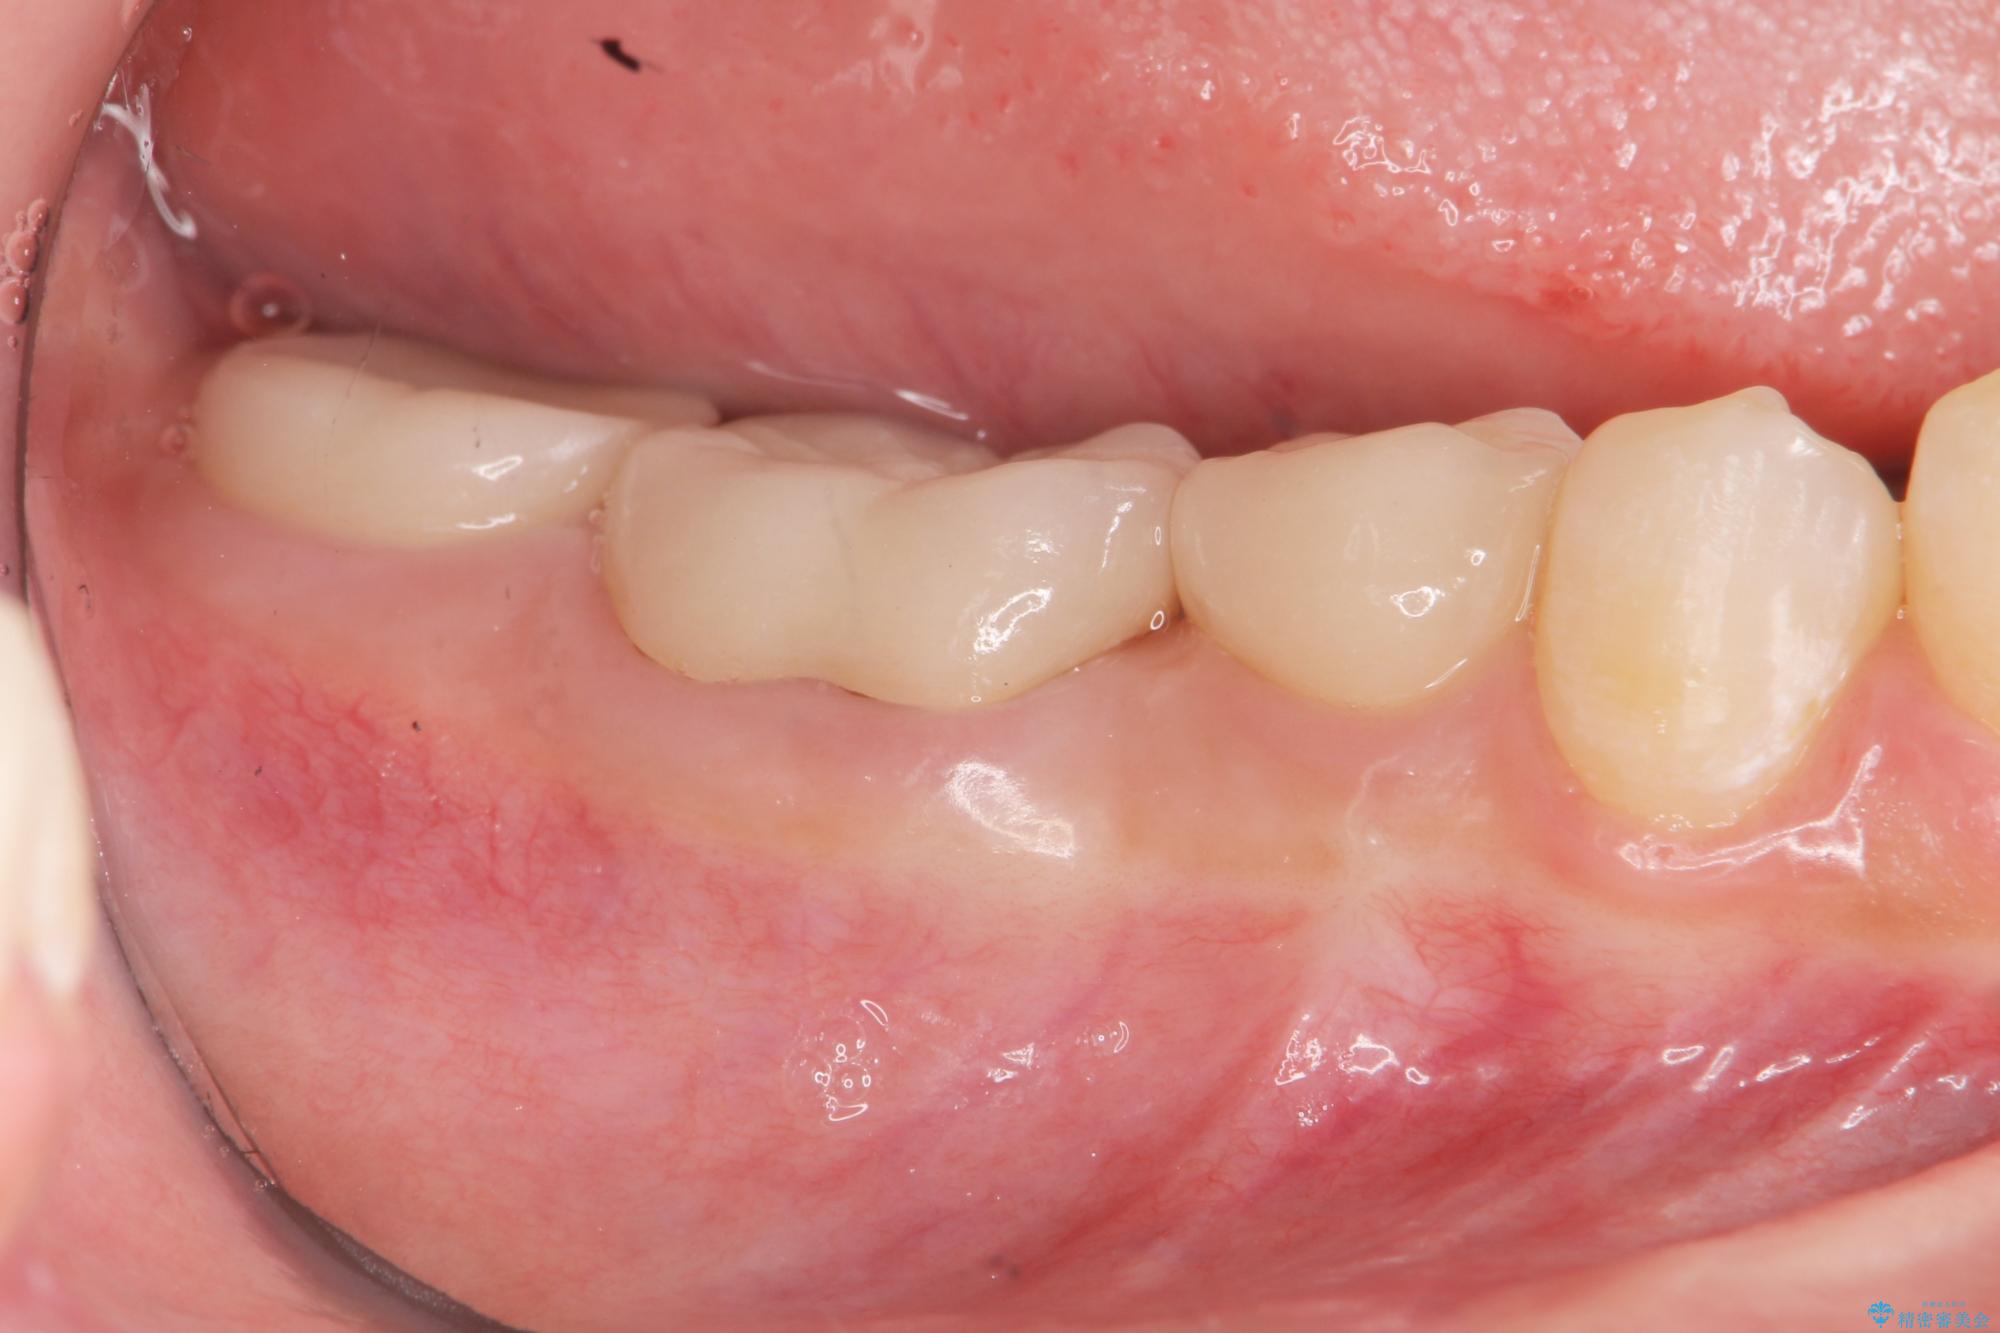

歯周外科を行うことで、歯ぐきの位置を下げ歯の高さを作り出し安定したクラウンの装着が可能となります。また同時に舌の邪魔となっていた骨隆起の除去を行うこととしました。

- 37.4万円(ジルコニアクラウン×2・仮歯×2・歯周外科手術)費用は治療当時の料金となります